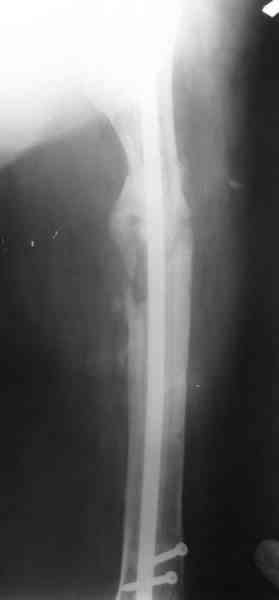

В настоящее время наш пациент ( см. http://weborto.net/forum/1177351385/) ходит с одним костылем. У него периодически открывается свищ на задне-наружной поверхности бедра с умеренным серозно-гнойным отделяемым. Температура тела и анализы нормальные. На рентгенограммах имеются признаки консолидации ложного сустава.

Иллюстрации:

1, 2, 3, 4 - рентгенограммы бедра от 8 августа этого года (через четыре месяца после операции);

Вчера наш пациент был на контрольном осмотре. Вроде все идет нормально. Рентгенограммы от 25 сентября 2007 г. (прошло 5 месяцев после операции) прилагаю.